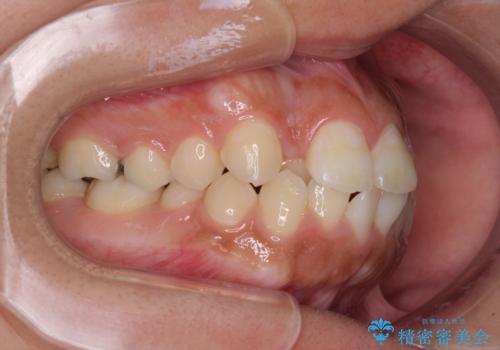

急速拡大とワイヤー抜歯矯正で唇を閉じやすく

- 口元の突出感を気にして来院された患者様です。

デコボコと口元の突出感が認められたため、上下左右の第1小臼歯4本を抜歯してのワイヤー矯正を行うこととしました。

上顎歯列の横幅が狭く、下顎大臼歯の歯軸が舌側に倒れていたため、急速拡大装置により上顎骨を側方に拡大し、咬み合わせを改善することとしました。

上顎歯列幅を拡大したことで、デコボコを容易に解消することができるようになったため、抜歯により得られたスペースを口元の突出感改善に利用することができました。